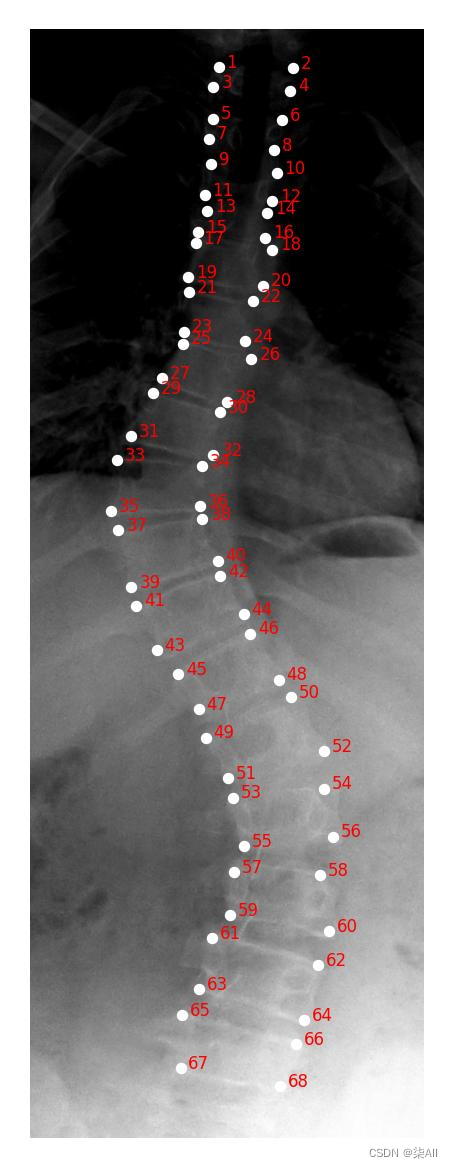

2、需要标注的关键点(冠状位、左右bending位)

冠状位(一共是标记72个关键点)

左右bending(一共也是标记72个关键点)

左bending和右bending是一样的,这里就做一个示范

3、冠状位标注结果